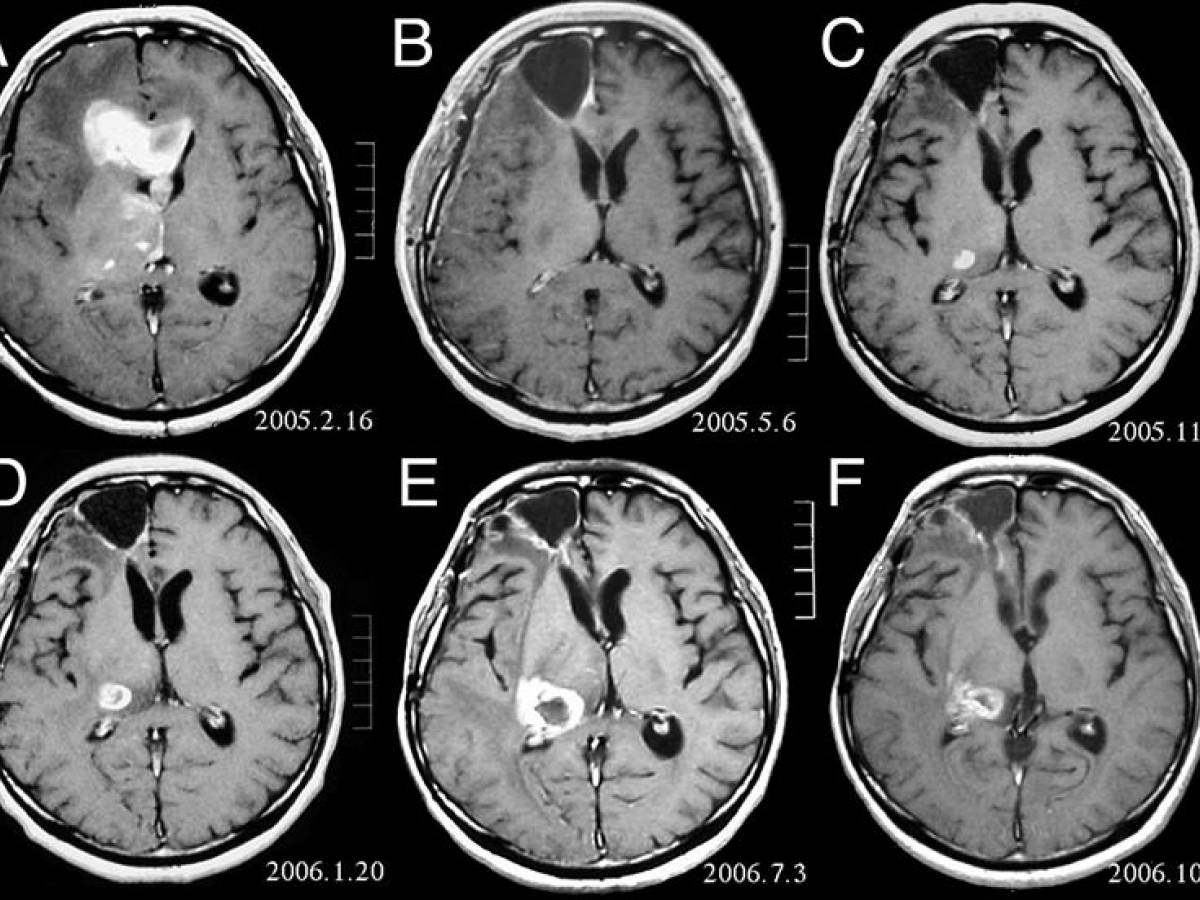

Who grade i

Who grade i 115 фотографий